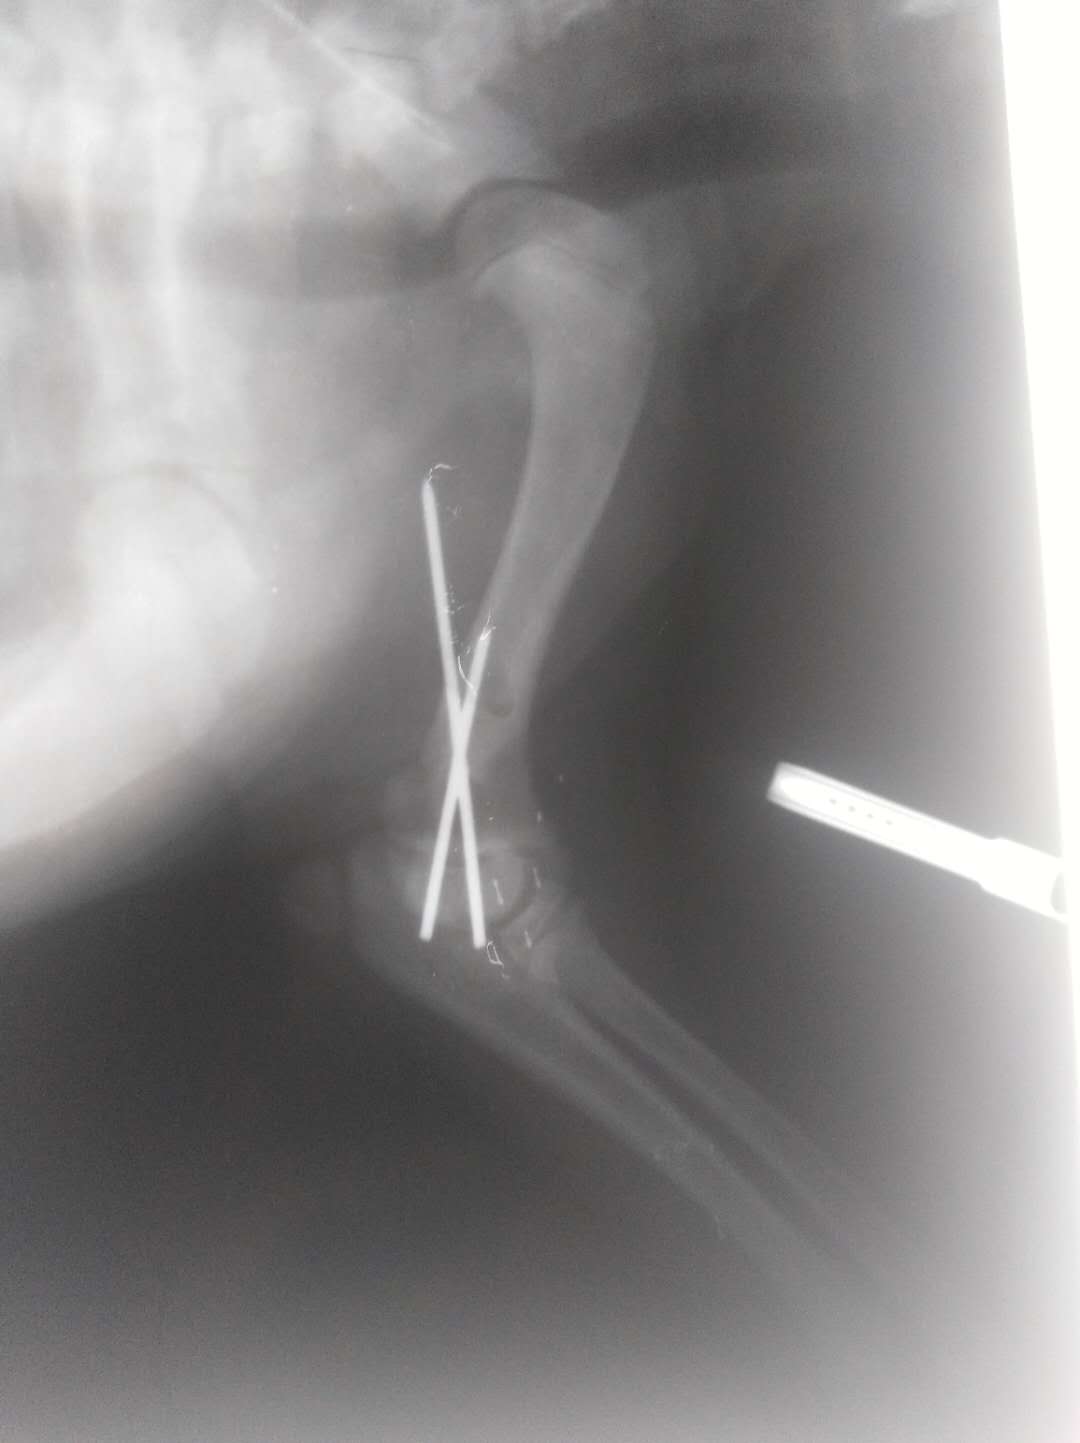

宠物土豆从移动的电动车上掉下来,出现左前肢跛行,腕关节弯曲不敢着地,关节肿大。经X光片显示,关节肘头与冠状骨斜骨折。经两个小时手术,将断骨联结,手术***成功。